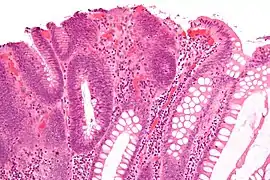

| Villous adenoma | 15%[16] to 40%[15] | Over 75% villous[14] | ![]() | |

Micrograph of a villous adenoma. These polyps are considered to have a high risk of malignant transformation. H&E stain.